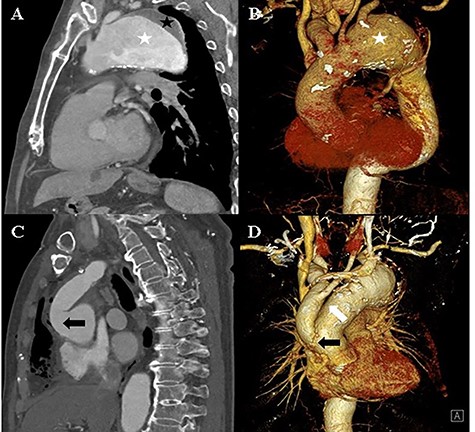

The patient remained asymptomatic with stable vital signs. A scheduled computed tomography was performed after 1 week. Computed tomography revealed a newly localized intimal dissecting flap at the proximal ascending aorta, which was located proximally, extending to the ostia of the right coronary artery. The patient underwent an emergency open repair operation. Circulatory arrest was established at a rectal temperature of 20°C, and cerebral perfusion was accomplished through the 18-mm graft cannula and left femoral artery cannulation. During gross examination, the 18-mm graft was seen detached from the ascending aorta, which was opened longitudinally, and an intimal tearing site was identified (Fig. 3). The dissection occurred transversely at the proximal stented site and was extended up to the sinotubular junction around the left coronary sinus and near the right coronary orifice in the right coronary and non-coronary sinuses. A Gelweave 28-mm straight graft was used, which was connected to the proximal aorta and reinforced with the double sandwich technique (Fig. 3). The distal anastomosis was performed, including a proximal resected valiant stent graft and the patient’s native aorta with a Teflon felt by sandwich technique. After the operation, the patient remained asymptomatic.

A: Intraoperative view of the transected ascending aorta due to the thoracic stent graft (black asterisk). B: The post-operation computed tomography image shows the replaced ascending aorta (white asterisk).